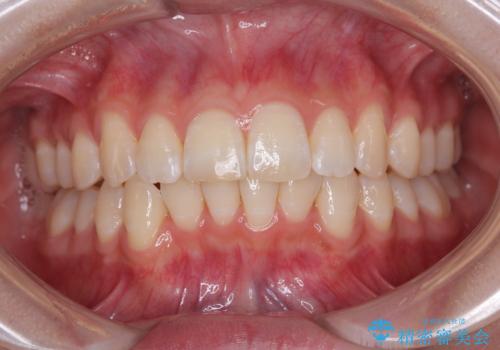

- 上下前歯の重なりを気にして来院された患者様です。

安価なインビザラインパッケージを用いての治療を希望されており、デコボコの程度が中等度であったため、インビザライン・モデレートを用いて矯正治療を行うこととしました。

インビザライン・モデレートは、製作できるアライナーの枚数に制限があるため、移動可能な量に限りがあるものの、インビザライン・ライトよりも枚数が多いため、幅広い症例に対応可能です。